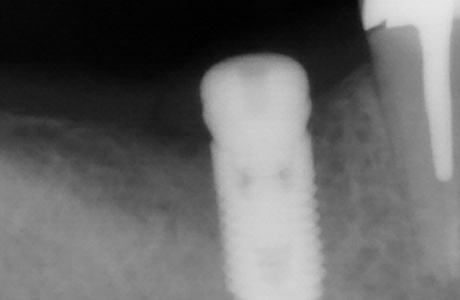

Установки импланта Alpha Bio в позицию зуба 4.6 «под ключ» для восстановления жевательной функцииСмотреть работуСрок лечения:30 минутСумма лечения:44 350 руб.